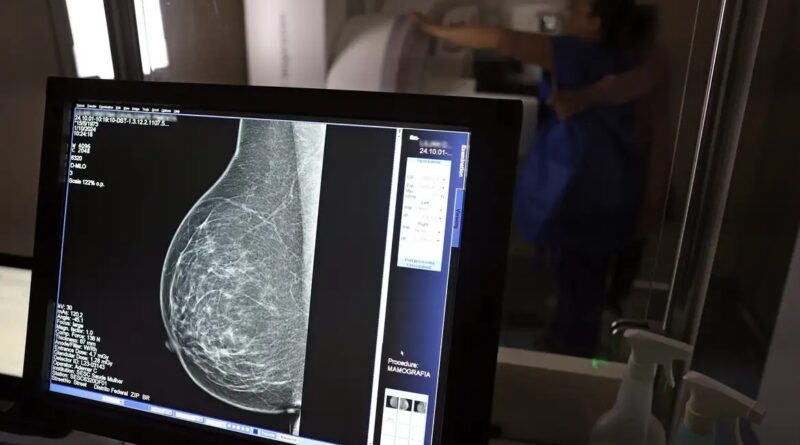

Governo Federal sanciona lei que amplia acesso das mulheres ao exame de mamografia fornecido pelo SUS

O texto determina que o exame de mamografia será garantido a todas as mulheres a partir dos 40 anos, conforme diretrizes do Ministério da Saúde, que poderão estender o procedimento a outras faixas etárias.